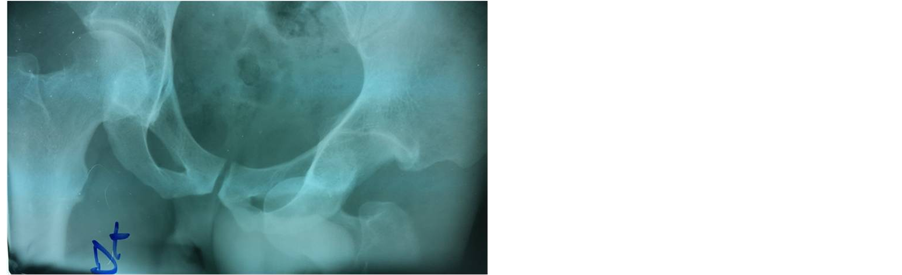

Mr. CA was a 26-year-old patient who was hospitalized on February 7th 2004 for a right hip injury following a road traffic accident. He had no medical history and in the circumstances of the accident, he was carrying his cart from the front when a car hit the back of his cart. Immediately, he felt a sharp pain and an absolute functional impotence of the limb. Clinical examination of the same limb revealed abduction, an external rotation and flexion at the hip. Standard radiographs confirmed obturator dislocation (Figure 2). Closed reduction under general

Figure 2. Anteroposterior X-ray of the pelvis showing a left obturator dislocation (patient 2).

anaesthesia was achieved 24 hours after the injury, followed by 10 days of bed traction. Control plain X-rays obtained 24 months later showed no signs of avascular necrosis.